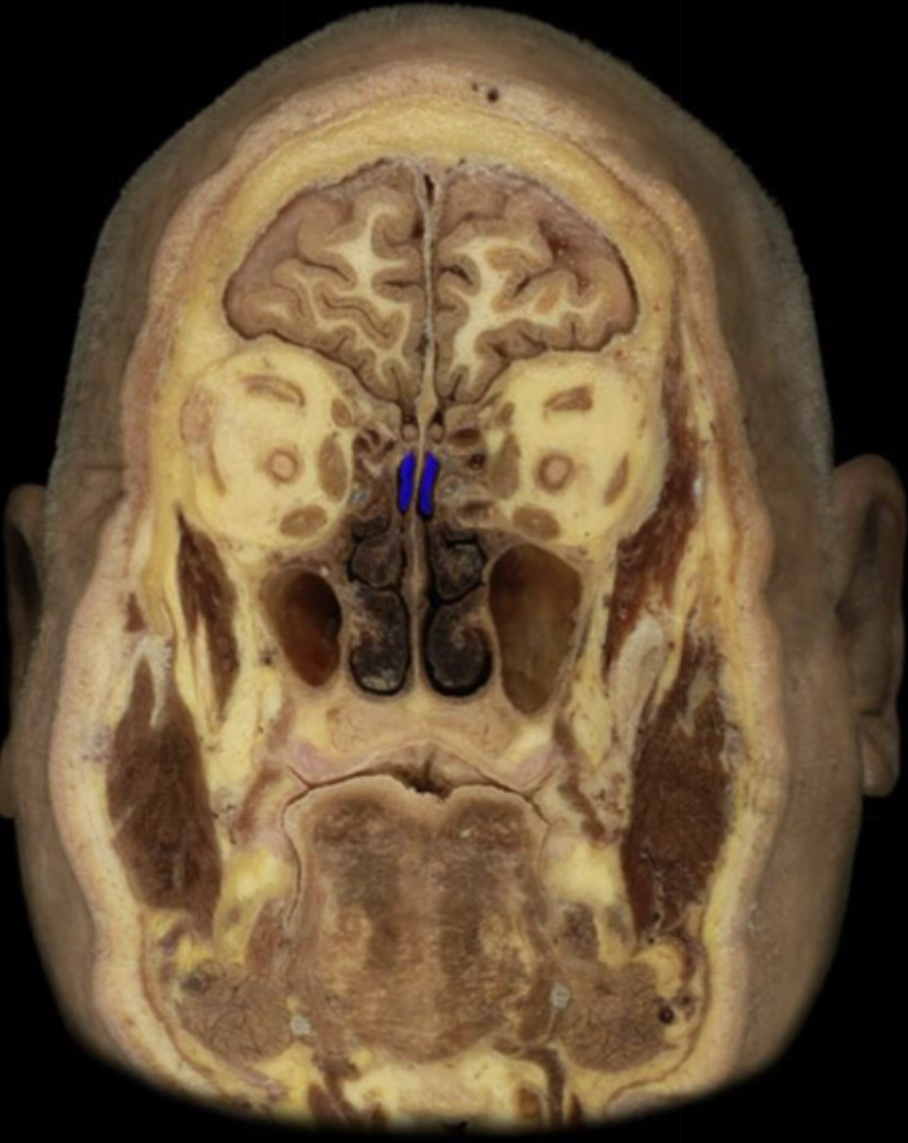

What structure is highlighted in blue?

Inferior nasal concha